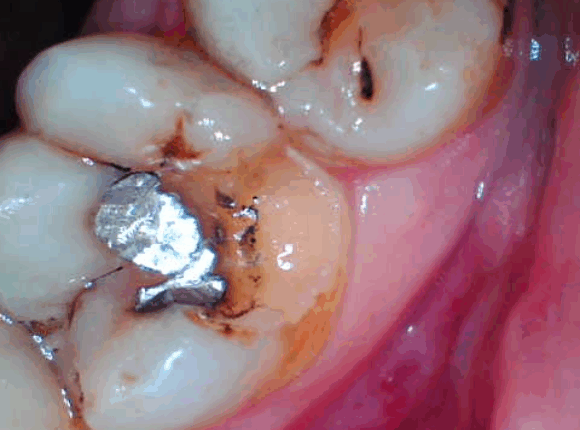

Though bonding helps many patients achieve stunning results, it has some drawbacks. Your dentist will decide if you need crowns, veneers, onlays, or inlays in place of bonding. In comparison to porcelain restorations, teeth bonding has the following drawbacks.

- It is less ideal for filling extensive defects or broken-down, decayed teeth.

- If you have had a root canal, your tooth might be too brittle to support a bond. The composite resin will be less supportive than what is necessary to maintain the tooth’s structure.